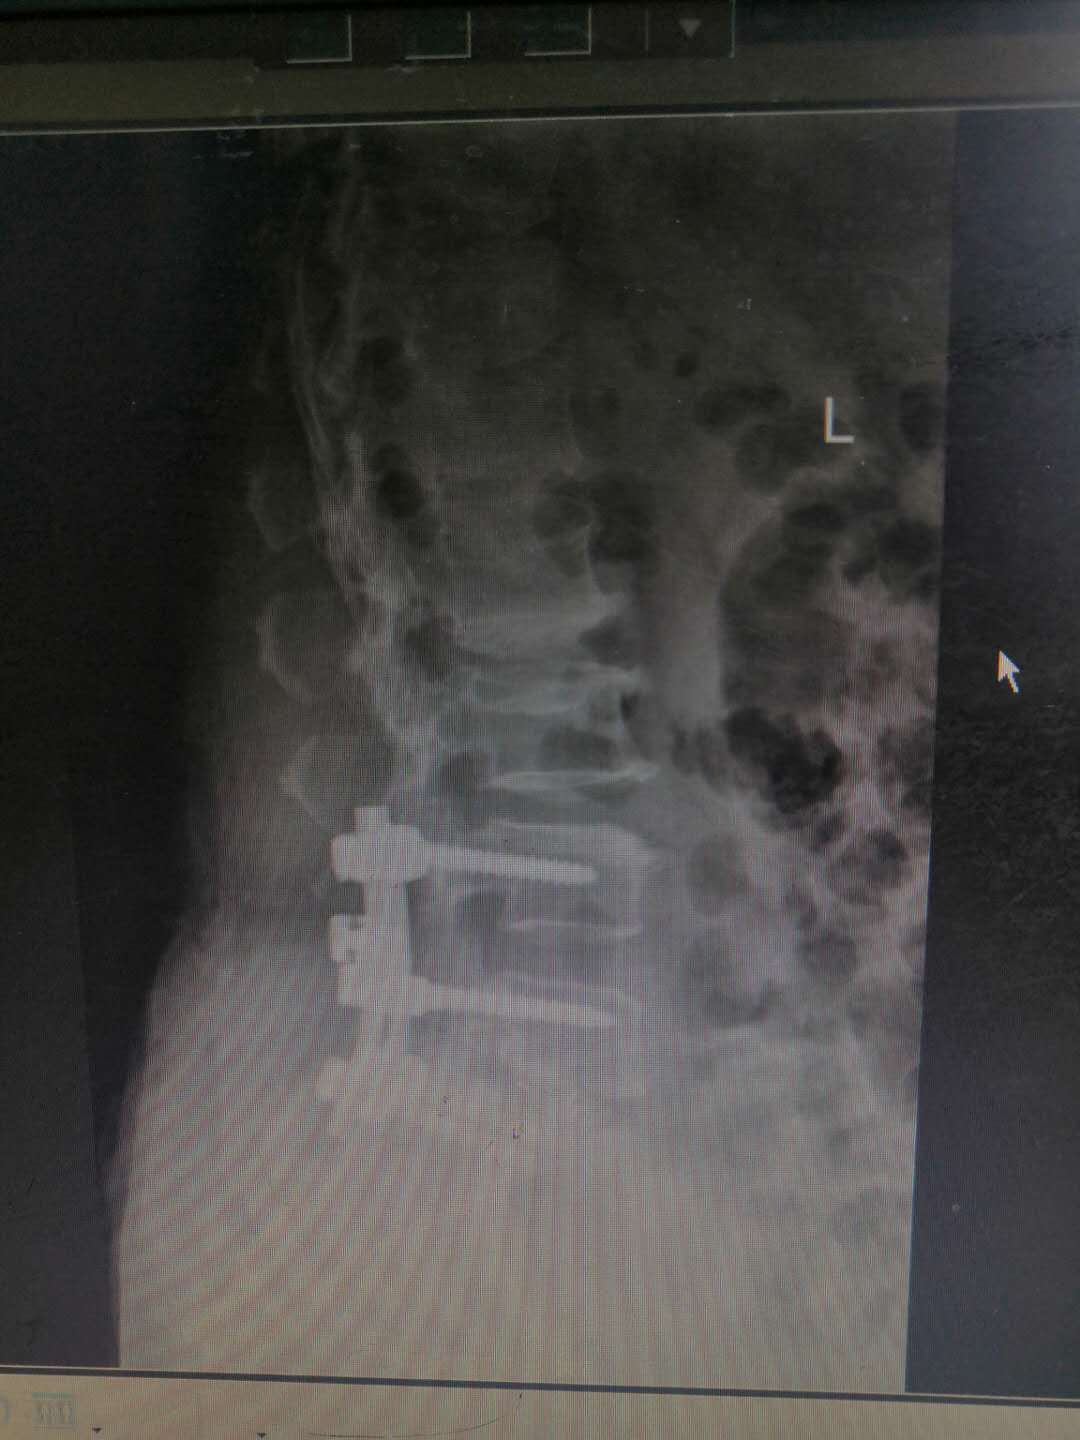

患   者:杨某,女,56岁。

主   诉:因反复腰痛伴右下肢疼痛麻木8年,加重6月,入院治疗。

现病史:缘于8年前开始无明显诱因出现腰部疼痛,呈间歇性胀痛,持续时间数分钟至数小时不等,放射至右下肢,伴右下肢麻木,此后症状反复出现,持续时间数小时至数天不等,劳累后加重,休息后缓解,6月前加重,并出现间歇性跛行,目前行走约200米左右需休息后方能继续行走,在当地医院治疗(药物+理疗)后效果欠佳,现特至我院就诊。

专科检查:颈胸椎各棘突无明显压痛,颈部活动正常,L3-5棘突及椎旁存轻压痛及叩击痛,疼痛无放射,腰部屈伸活动轻度受限,右下肢直腿抬高试验阳性(40度),加强试验阳性,双侧跟臀试验阴性,拾物实验阴性,右侧股四头肌、右足拇背伸肌力约4级,右小腿后、外侧、足背、足底感觉较左侧减退,肢端血运正常。

术前影像资料:

诊       断:

腰椎滑脱症(腰5向前III度)并腰椎管狭窄症。

治疗方案:

入院讨论后予在全麻下行腰4、5、骶1椎弓根螺钉内固定+腰5滑脱复位+腰5/骶1髓核摘除并Cage植入椎间植骨融合术。

术后影像资料: